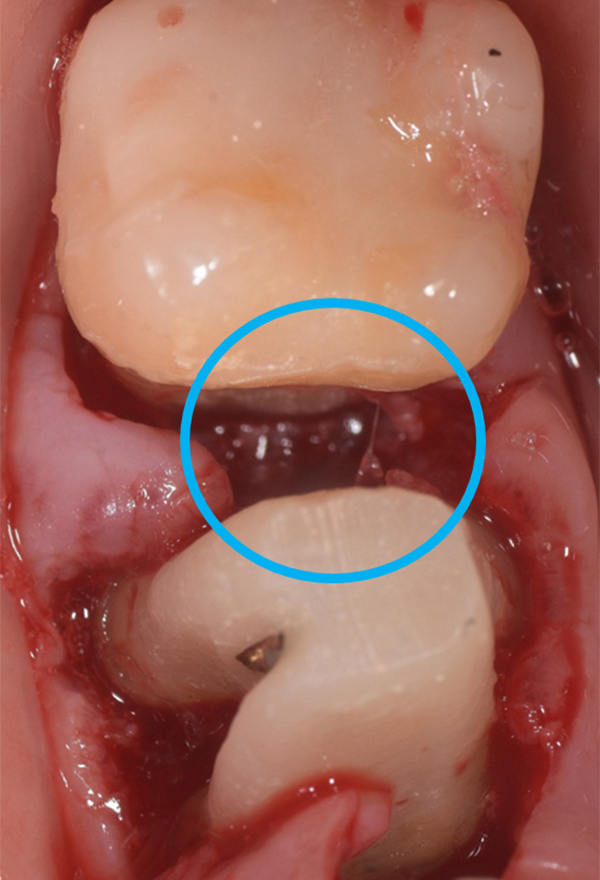

軽度〜中程度レベルの歯周炎であれば、ここで改善が見られますが、中程度以上の歯周炎の場合は、その後に歯周外科処置を行うことが多いです。なぜなら、歯周ポケットが5mm以上ある部位にSRPを行っても多くの歯石の取り残しがあるという報告があるため、深い歯周ポケットを有する患者さんに対しては歯周外科処置を行います。歯周外科処置で一般的な術式は歯肉剥離掻爬術です。痛く無いように麻酔(局所麻酔)をした後、歯肉をメスで切り(切開)、切った歯肉を骨から剥がし(剥離)、歯の根に付着した歯石、歯槽骨の形態などが直接見える状態で、歯石や感染物の除去を行います。その際必要であれば、その後に患者さん自身で清掃がしやすいように骨の形態を整える歯槽骨整形も行います。最後に切った部分を縫って(縫合)処置を終わります。

歯周組織再生療法といい、先に記しました通り、GTR法、エムドゲインを使用した方法、リグロスを使用した方法といくつかあります。GTR(Guided Tissue Regeneration)法とは、歯周外科処置と同様に歯肉をメスで切り(切開)、切った歯肉を骨から剥がし(剥離)、歯の根に付着した歯石、歯槽骨の形態などが直接見える状態で、歯石や感染物の除去を行います。その後、骨が吸収して失われた部分にこのバリア膜で覆い縫って(縫合)処置を終わります。バリア膜で覆うことで、歯肉などの軟組織が骨の中へ直接入り込むことを防ぎ、新しい血管が新生され、歯周組織の再生を促します。治療後およそ6ヶ月待ちます。